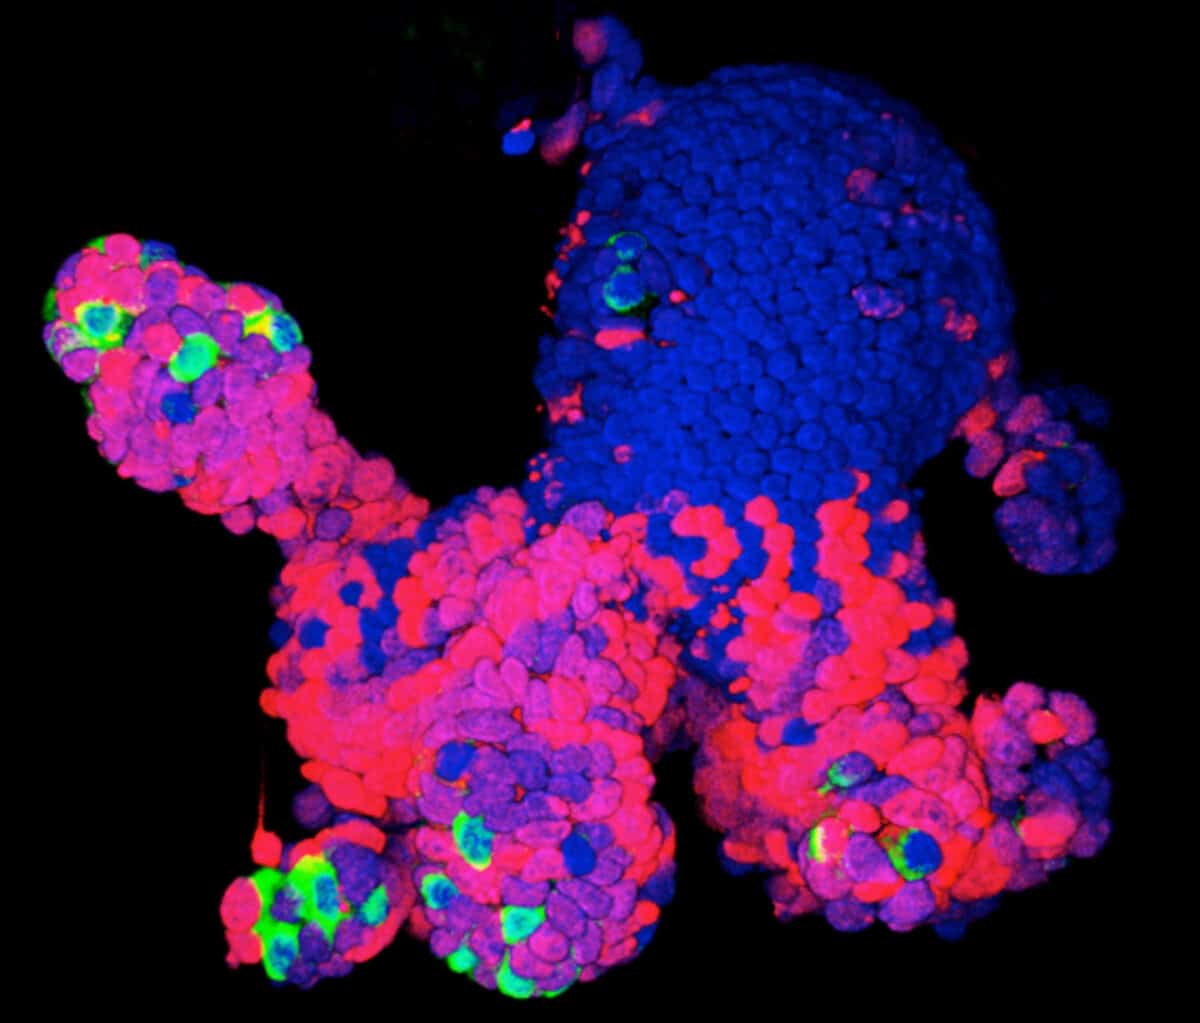

During the next two to three months, the cells began to organize themselves into layers and clusters of different cell types, paralleling what happens during the first eight to 10 weeks of human fetal brain development. Some cells differentiated themselves into various types of the nerve cells (neurons) found in several brain regions, while others remained “neural progenitors,” creating a reservoir of potential neurons to be used later. Producing such self-assembling organoids “doesn’t require any super-sophisticated bioengineering,” Knoblich told Nature in 2015. “We just let the cells do what they want to do, and they make a brain.”

In the organoids that Lancaster had derived from a healthy person, the growth of the hindbrain slowed as the forebrain grew—reflecting what happens as a normal human fetal brain develops. Organoids grown from the cells of a patient carrying the gene for severe microcephaly, however, didn’t grow as large because those brain regions didn’t develop properly. Further research showed that too many neural progenitors in these organoids had become neurons early on, leaving the developing brain without the resources it would have used to enlarge the forebrain.

For that study, Arlotta was looking at a stage of brain development later than the one studied in the microcephaly and Zika experiments, which modeled only what happens early on during pregnancy. So she modified the Lancaster system to allow her organoids to survive and develop in culture for longer than anyone else—more than nine months.

During gestation, a human brain generates the kinds of cells and circuits needed to carry information. Neurons, the main communicators, form connections with other neurons via structures called dendrites, which receive the incoming electrical signals used to communicate information within and beyond the brain, and axons that pass along the message to the next cell across synapses, the gaps between cells. “These long periods of development in the dish allow many types of cells to form and mature. Importantly, neurons acquire properties of mature cells, most notably dendritic spines, the structures that form on dendrites and receive synapses,” she says.